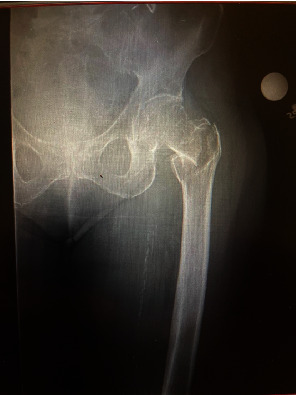

介绍:髋关节转子间骨折的手术治疗是一种常见手术,术中并发症发生率较低。在不切开复位的情况下放置髓内钉,血管损伤非常罕见。在髋部骨折闭合复位和髓内钉置入术后,远端联锁螺钉水平出现直接动脉损伤和活动性出血的病例极少见。我们报告了一例这样的病例。病例介绍:一名 88 岁的女性因左侧转子间髋部骨折到急诊科就诊。按计划对左侧髋部骨折进行了闭合复位并用头髓内钉固定,术中没有出现任何明显的技术问题。术中患者病情保持稳定。无需进行切开复位。术后,患者出现失血性休克,需要大量输血。血管造影显示,髓内钉远端锁定螺钉处出现肌肉内血肿,并伴有活动性外渗。患者随后需要进行栓塞治疗。术后九天,她开始服用伊利奎斯(Eliquis)预防深静脉血栓形成,目前已能独立行走,血肿也有消退迹象。讨论股深动脉损伤可能源于手术过程中的各种机制。动脉粥样硬化会使患者因血管僵硬而面临更高的并发症风险。在本病例中,钻孔超出股内侧皮质被认为是导致动脉损伤的原因。结论:在手术过程中应注意防止钻头陷入股内侧皮质之外。谨慎观察患者的生命体征和临床病程可及早发现血管并发症。

Introduction: Surgical management of intertrochanteric hip fractures is a common surgery with low rates of intraoperative complications. Vascular injuries are exceptionally rare when placing an intramedullary nail without open reduction. There are very few reported cases of direct arterial injury and active bleed at the level of the distal interlocking screw following closed reduction and intramedullary nailing of a hip fracture. We report one such case. Case Presentation: An 88-year-old female presented to the emergency department with a left intertrochanteric hip fracture. Closed reduction with a cephalomedullary nail fixation of the left hip fracture occurred as planned without any obvious intraoperative technical issues. The patient remained stable intraoperatively. No open reduction was required. Postoperatively, the patient developed hemorrhagic shock and required massive transfusion protocol. Angiography demonstrated an intramuscular hematoma at the level of the distal intramedullary nail interlocking screw with active extravasation. The patient subsequently required embolization. Nine days following surgery, she began Eliquis for DVT prophylaxis and was ambulating independently with signs of hematoma resolution. Discussion: Profunda femoris artery injury can stem from various mechanisms during surgery. Atherosclerosis places patients at a higher risk of complication due to rigid vessels. In this case, it is believed that drilling beyond the medial femoral cortex led to the arterial injury. Conclusion: Care should be taken to prevent drills from plunging beyond the medial femoral cortex during surgery. Cautious observation of patient's vitals and clinical course can allow for early detection of vascular complication.